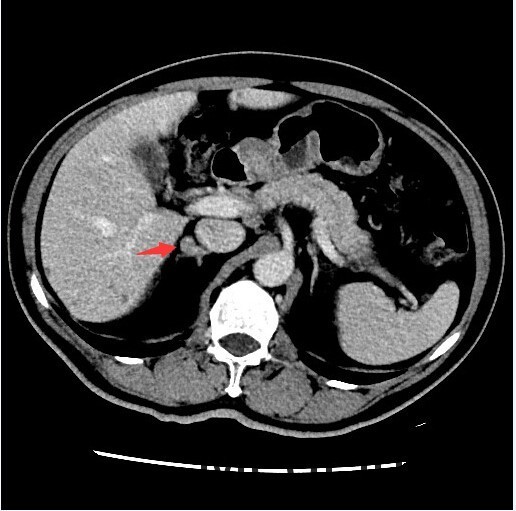

查体::血压:140/80mmHg。双肾区无红肿、隆起,无叩痛,双侧肋脊点、肋腰点无压痛。 辅查:双肾上腺CT提示:右侧肾上腺结节,考虑腺瘤可能性大,右侧小囊肿,肝内多发囊肿。

随访:术后病理示:考虑为肾上腺皮质腺瘤。 讨论:肾上腺腺瘤是来源肾上腺皮质的腺瘤,根据临床表现不同,临床分为无功能性腺瘤、功能性腺瘤(又分为Cushing腺瘤和Conn腺瘤),本例患者具有乏力、低血钾和高血压等醛固酮增多症表现,应属于Conn腺瘤。该类腺瘤一般表现为肾上腺区的孤立性小肿块,边界清楚,大小一般不超过2cm,由于富含脂质,CT平扫密度接近于水样密度,增强扫描轻度强化,本例的CT影响表现基本符合。